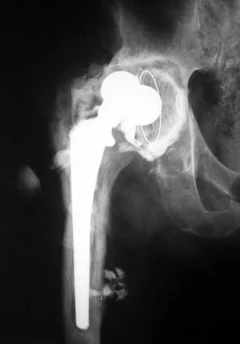

Как видно на приведенной рентгенограмме, после удаления эндопротеза остаётся "пустое место" в области бывшего тазобедренного сустава.

Нестабильность компонентов эндопротеза (асептическая нестабильность, расшатывание эндопротеза)

При стоянии или ходьбе на эндопротез ложится большая нагрузка, в соединении между костью и эндопротезом происходят микродвижения. Вследствие этого эндопротез расшатывается. Может расшататься как ножка (бедренный компонент), так и чашка (вертлужный компонент) протеза. Ножка эндопротеза может разрушить стенку кости, в которой расположена - возникает перипротезный (парапротезный) перелом.

При развившейся нестабильности эндопротеза требуется повторная операция - ревизионное эндопротезирование.